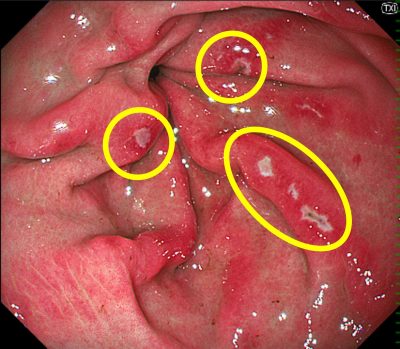

胃カメラ(上部消化管内視鏡)

胃の中には出血による血糊が多発しており、

胃の出口付近(前庭部)に出血源と思われる多発びらん(浅い傷)を確認。

➡ 腰痛に対して市販の痛み止め(NSAIDs)を1週間ほど服用しているとのことで、薬剤性胃粘膜障害と判断しました。